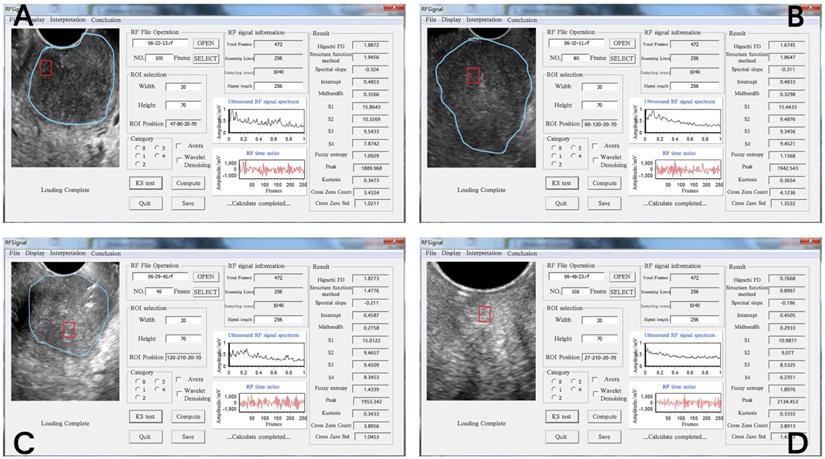

In the current study, the sonographer outlined the cancerous nodule region in the B-mode ultrasound image to allow the programmer to select the cancerous ROI accurately. The ROI size was 70 × 20 mm. We used the first 256 frames of the back scattering echo RF signal to form the 1400 RF time series, which was used to extract the tissue characterizing features. The RF time series signal analysis software developed by the team was used for quantitative analysis of the ROI [13]. The FD, frequency domain, and time domain features of the RF time series were extracted, including 14 parameters in total (Figure 1). The calculation methods for extracting all parameters are detailed in Supplementary. Among them, SFD and Higuchi FD belong to FD parameters; slope, intercept, midbandfit, S1, S2, S3, and S4 belong to frequency domain parameters; and fuzzy entropy, kurtosis, peak value, cross zero count, and cross zero Std are time domain parameters.

Figure 1

Operation interface for extracting RF time series parameters from cervical tissue. The four images represent the diagrams of the extraction operation interface of the RF time series parameters of different pathological types of cervical tissue. The ultrasound image of different cervical tissues is on the left of each interface; the blue line outlines the cervical cancer lesion area, and the red line outlines the ROI. The middle area of the interface is the respective RF time series spectrogram. The respective 14 RF time series parameter values are shown on the right side of the interface diagram. The pathological types of the four ROIs were as follows: (A) poorly differentiated cervical squamous cell carcinoma, (B) middle-low differentiated cervical squamous cell carcinoma, (C) middle differentiated cervical squamous cell carcinoma, (D) normal cervix with a cytology negative for intraepithelial lesion or malignancy.